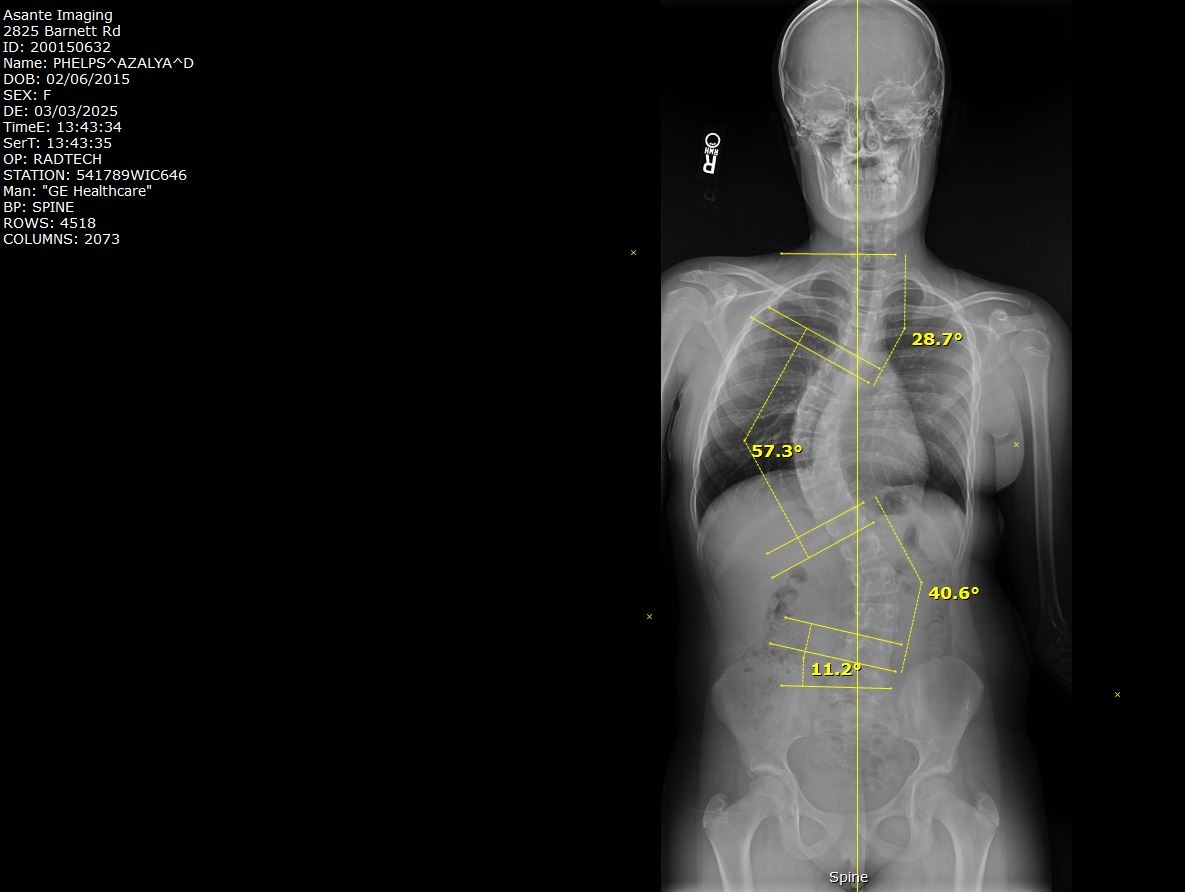

Her journey began just 2 months into her time on Earth with us. She was diagnosed with Cystic Fibrosis, and through her maintenance around that disease, we discovered the curvature in Azalya’s spine. At the time, we were told to just wait and see... little did we know, that is the last thing you want to do with a curve in your back while still growing. By the time she was seen again, her curve had significantly worsened, and we were referred to a specialist.

Last winter, we saw the specialist and were told there was nothing that could be done to reverse a scoliosis curve — and not to believe anyone who says otherwise. We were told she would need back surgery. We were determined to get a second opinion, and through some recommendations, we found the Scoliosis Care Center in San Jose.

After our initial inquiry and their team reviewing Azalya’s x-rays, things moved quickly. Due to the significance of her curvature and her age, we were urged to start treatments immediately. That meant school, dance, soccer, and Spring Break would have to wait. Two weeks later, we were in San Jose beginning our journey.